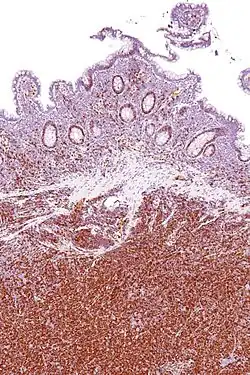

Immunohistochemical staining of cyclin D1 antibodies is used to diagnose mantle cell lymphoma.

Chromosomal translocation around the cyclin D1 gene locus is often seen in B mantle cell lymphoma. In mantle cell lymphoma, cyclin D1 is translocated to the IgH promoter[56] leading to cyclin D1 overexpression. Chromosomal translocation of the cyclin D1 gene locus is also observed in 15–20% of multiple myelomas.[57][58]